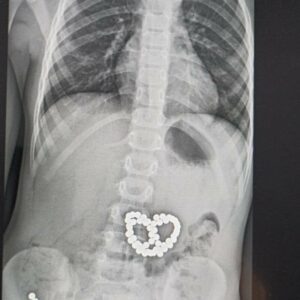

Другий випадок був набагато складнішим – дитина проковтнула понад 50 магнітних кульок. Ендоскопістам, хірургам та анестезіологу довелося добряче «попітніти», написав лікар Сергій Щудро.